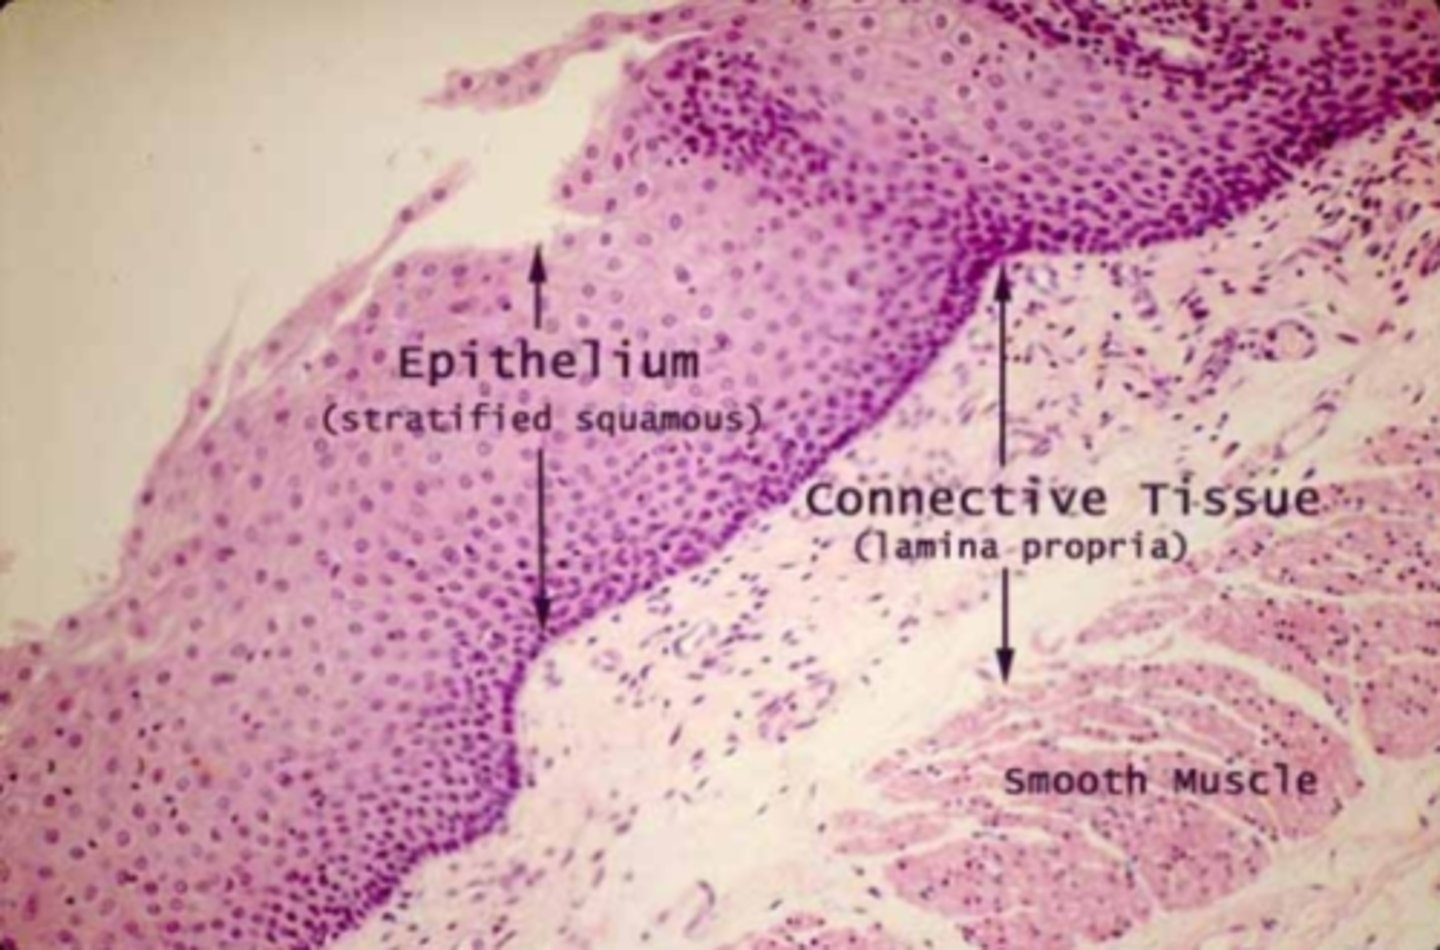

Esophagus

What is this?